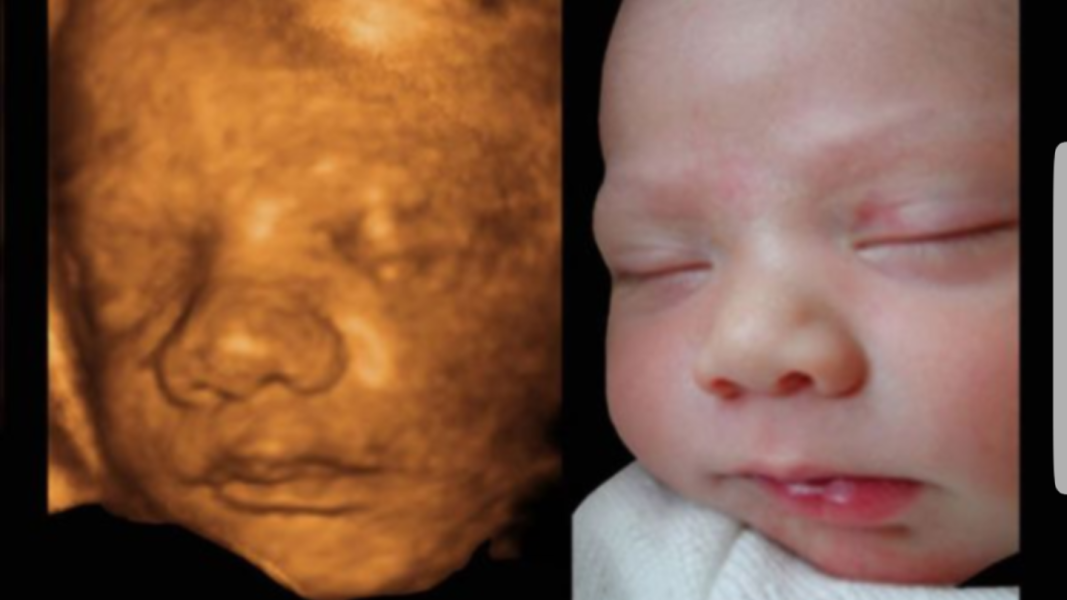

Мамочки, кто делал 3d узи, в итоге фотки оказались похожи или нет на родившегося ребетеночка?)) А то сделали мы 3d узи в 25 недель, а там шнёбель👃на пол экрана🤣🤣 Волнуемся, 🙈что за неизвестная кровь предков взыграла в нашем чаде😍

P.S. фотка взята просто из интернета.

На картинке что вы приложили на 3д тоже кажется большой нос, а вживую вполне милый носик) так что не волнуйтесь)

У нас тоже носик казался большим😒а на деле оказался маленькой кнопкой ))

У нас только губы похожи в 29 недель. Вообще мало сходства тк на таких сроках у мелких еще нет почти подкожного жира. А фото в посте скорее всего уже рядом с родами сделано .

Вот и у нас шнобель на узи был.Я чуть не плакала.В живую шнобеля нет.